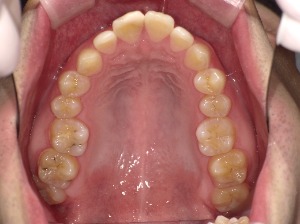

歯列のアーチとは、上・下の歯が並んでいるカーブの形のことです。

上から見たとき、歯が半円状に並んでいる様子をイメージしてください。

| V字型(狭め) | 尖った形 | 顎が細く見えるが、口元が窮屈な印象に |

アーチ形状は、顎の骨の形・歯の大きさ・舌の位置・筋肉の使い方などによって決まります。